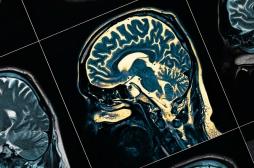

LES MALADIES

J'AI MAL

J ai Mal Bras et mains Bras et mains Tête et cou Torse et haut du dos Jambes et pied